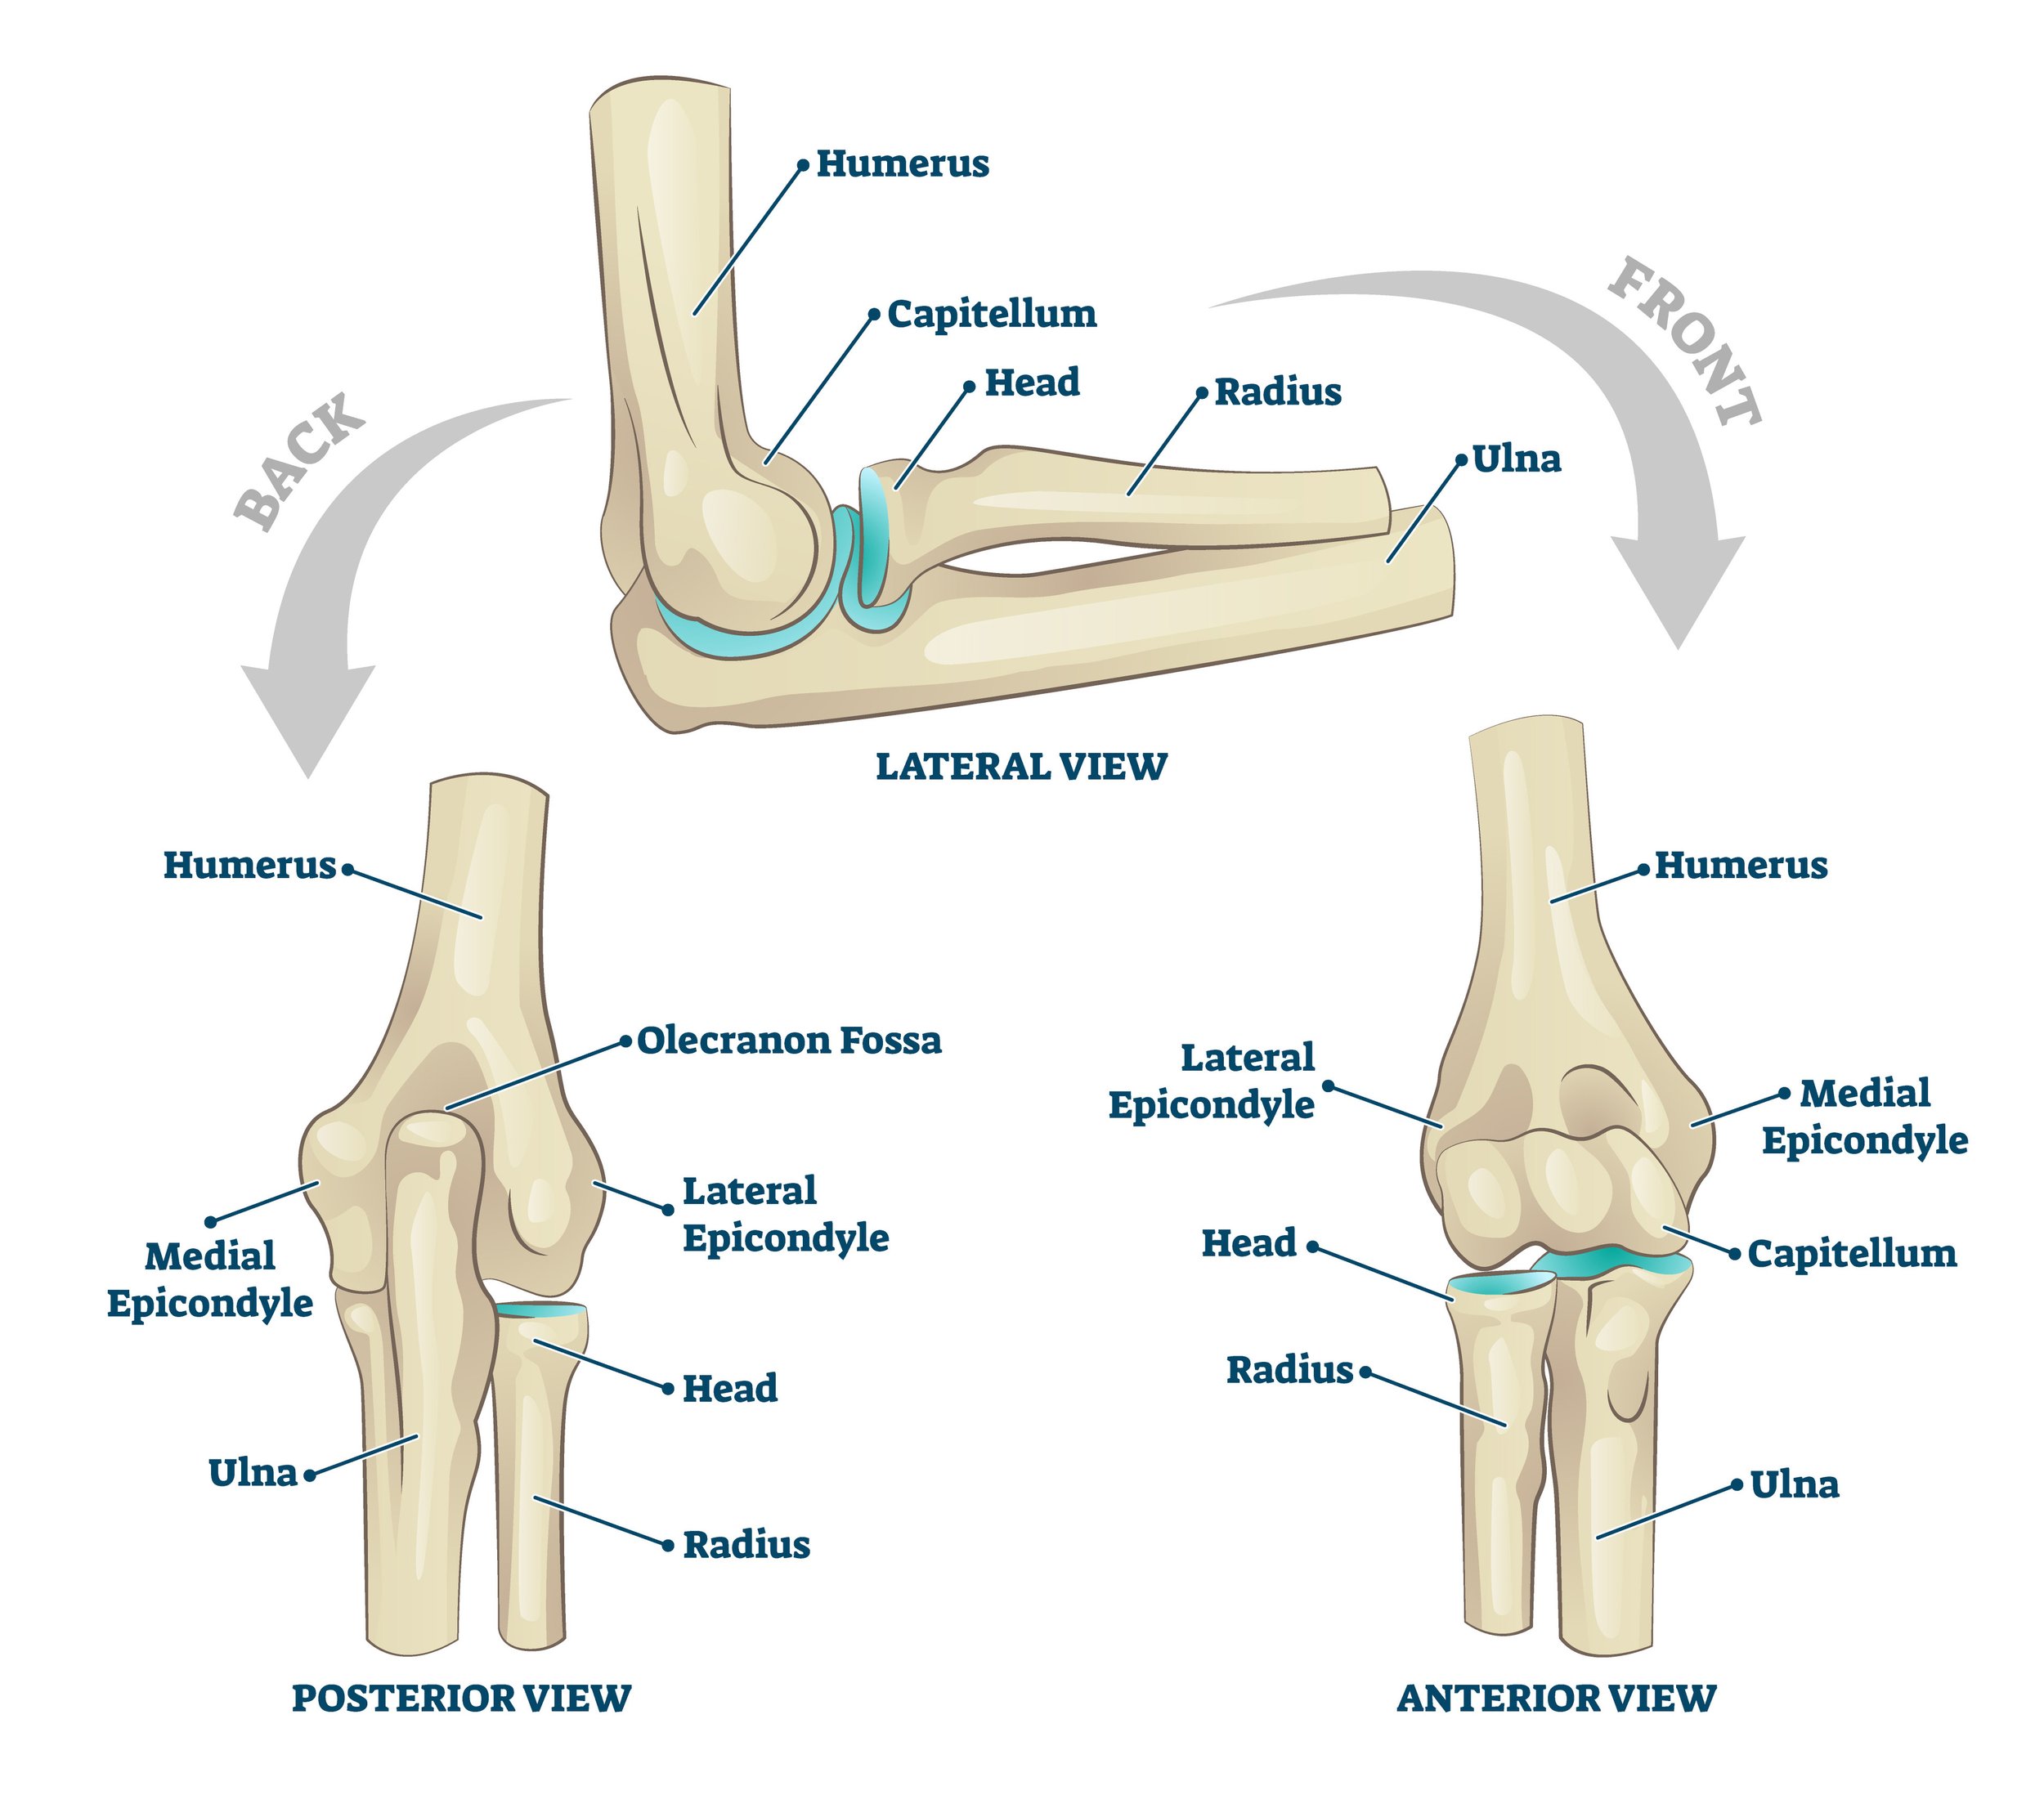

Medial Elbow Anatomy: The Basics

To understand what Little League elbow (LLE) is, you need a rough grasp of the complex anatomy of the medial elbow. Below is an abbreviated list of the relevant structures that play a role in LLE.

Bones:

Medial Epicondyle: The large bone felt on the inside of the elbow. It is the attachment site for the forearm/finger muscles that make a fist and flex your wrist. The ulnar collateral ligament (see below) also attaches here.

Medial Epicondyle Apophysis (growth plate): The growth plate located on the medial epicondyle at the inside of the elbow. This is the structure injured in LLE.

Muscles:

Wrist/Finger Flexors: The group of muscles in charge of flexing the wrist and fingers (heavily utilized during the throwing motion).

Common Flexor tendon: The tendon that connects the flexor muscle group to the inside elbow (medial epicondyle).Ligaments:

Ulnar collateral ligament (UCL): aka the Tommy John ligament. The ligament that helps hold the elbow together and connects the upper and lower arm bones. This is the ligament commonly injured in adult pitchers, but less commonly involved in youth athletics and Little League elbow. It is heavily stressed during the throwing motion.